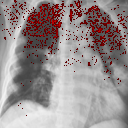

II.6 Saliency maps

Saliency maps assign pixels in an image according to their contribution (a class score derivative) to the final output of a CNN-based classifier. Another interpretation of saliency maps is that the magnitude of the derivative indicates which pixels need to be changed the least to affect the class score the most Simonyan et al. (2014). A saliency map is extracted for a given image and class label by back-propagation procedure. This technique helps extract information from the black box model and visualise how it interprets the given data. Saliency maps are one of the essential tools that allow verifying that classification results do not depend on artefacts from the training set, so-called "shortcuts", and help in understanding where observed misclassifications come from Alqaraawi et al. (2020). Saliency maps for instance can be utilised to identify whether the classification of COVID-19 is based on the infected regions of the lungs, rather than being influenced by image artefacts such as drains or specific body positioning for the X-ray scan.

To better illustrate the most important features of analysed samples in the view of the two considered CNN classifiers a state-of-the-art AI-explainable approach known as Image-Specific Class Saliency Simonyan et al. (2014) is applied. The maps are obtained for the most accurate model: EfficientNet-B0 trained on the balanced dataset (Results). To denoise the results and make them more readable the top 10 most valuable features were marked on the source image.

To validate that results are not biased by models focusing on non-biomarkers saliency maps are used. The regions of interest of correctly TOP-1 predicted class on the representative test images are shown in Fig. 12. It is clear that the saliency maps often indicate the lung region as important, moreover, they do not concentrate on artificial indicators like the drain visible in Fig. 12d. That suggests that the model takes into account genuine lung lesions.

We successfully validated that the models did not learn so-called "shortcuts" using saliency maps. However, the model returns some areas of concern, especially in normal and viral pneumonia classes. The CNN focuses on the lower parts of the lungs and body parts behind them like a diaphragm, which is definitely not a bio-indicator in this case. Some of the indicated features can be seen under armpits, a similar result to saliency maps obtained by DeGrave et al. DeGrave et al. (2021). While such effects could indicate that CNN has learned to recognise "shortcuts", the majority of the attention is focused in the lungs area as one would expect. To verify this is not a significant effect maps for misclassified images are analysed (Figs. 12e and 12e), e.g image for COVID-19 positive case classified as normal. No obvious differences from properly classified images are observed. While the CNNs locate the most important features in the lung area as expected they do not yield straight human interpretable imaging biomarkers. This highlights the still inseparable black-box limitation of the deep learning algorithms.